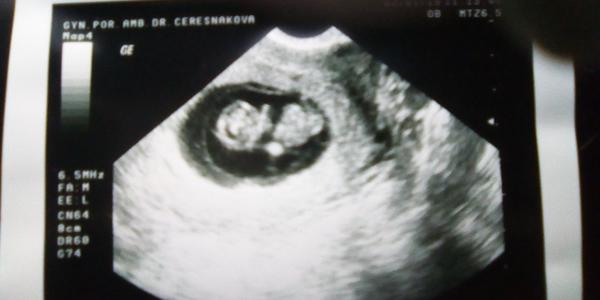

@marcetta_k no, moje doktorka dela utz pro zijsteni zacinajiciho tehotensvi uz v cca 6.tt - to jen potvrdi ze je tam dutinka znacici zacinajici tehu... Rovnou objedna na dalsi kontrolu za 2 tydny (cca na 8tt) aby byla jistota, ze se tehotensvi vyvyji a je videt tlukot srdicka - kdyz je to ok, tak v 10tt odbery a prvni poradna.... U prvni dcerky mi v tom 10tt ultrazvuk nedelala, ale dneska doktorka co tam byla na zaskoku mi ho udelala, tak uz mam i dve fotecky - z minule a z dnesni kontroly 🙂

@lucinkamarecek no, ono asi i zalezi na tom, jak kvalitni ultrazvuk doktor ma... ta moje ma takovy stary, srdicko v 6tt na nem jeste videt neni, jen cerny flek (dutinka) a v nem miniaturni bila carecka (embryjko)... asi proto pak dela dalsi kontrolu v tom 8tt, kdy uz to srdicko je videt krasne...

@lucinkamarecek No, ona Ceresnakova ma uz par let sama nejake zdravotni problemy a i manzela mela myslim dost nemocneho (chodila k ni i moje mamka a hodne si s ni povidala), ale ordinaci se porad snazi udrzet, proto tam ma skoro porad zaskok... Tu starsi doktorku jsem tam videla ted poprve, jinak vzdycky doktor Marek.... Krev mi brali ted na te posledni kontrole, to ti asi uz budou brat taky jak pujdes... Berou 3 ampule a zjistuje se z toho krevni skupina a pohlavne prenosny choroby + krevni obraz myslim... Vysledky budou na dalsi kontrole, jinak chcou moc, zmeri ti tlak a bude je zajimat vaha pred otehotnenim a aktualni vaha... Vse ti zapisou do prukazky a tu uz ti daji spolecne s Prenatal Boxem. Na screening posilaji na Veveri, ale daji ti jen letacek s kontaktem a musis si tam zavolat objednat se sama, to muzes klidne hned, je dobry se objednavat dostatecne predem, mivaji dost plno, zvlast pokud chces nejakeho konkretniho doktora.... U dcerky jsem to neresila, ke komu pujdu, ale dostala jsem se k doktorce, ktera byla takova stroha a neprijemna, tak ted jsem si vyzadala pana doktora Vlašína - mozna jsi o nem slysela - je to vyhlaseny doktor z Veveri, pry opravdu kapacita, vsehno peclive prohledne, vysvetli a dokaze uz kolem toho 13.tt spolehlive poznat pohlavi - aspon co jsem tak ve svem okoli slysela, tak se pry vzdy trefil....